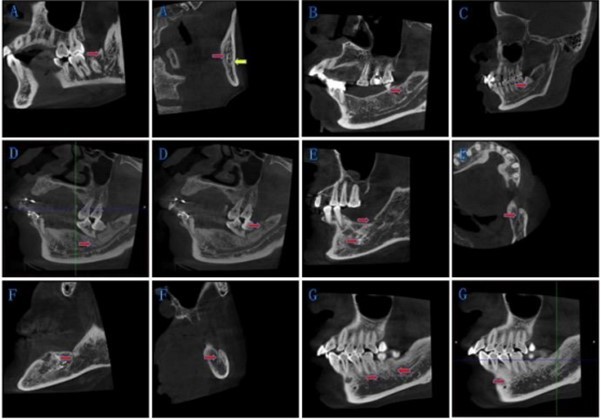

According to our rules, we divided BMC into four types. Type IA was bifurcations at the mandibular ramus, and retromolar foramen has been formed. Type IB was bifurcations at the mandibular ramus, and retromolar foramen has not been formed. We took those bifurcations at mandibular body as Type II. Type III was for bifurcations exist both at the mandibular body and the mandibular ramus on one side. Type IV for other circumstances. Details as following in Table 1 and Figure 2

Figure 2.New classification of BMC: The red arrow points to the bifurcations, and the yellow arrow points to the mandibular canal. (A) Type IA: Bifurcations at the mandibular ramus, and retromolar foramen has been formed. (B) Type IB: Bifurcations at the mandibular ramus, and retromolar foramen has not been formed. (C) Type II: Bifurcations at the mandibular body. (D)-(F) Type III: Bifurcations exist both at the mandibular body and the mandibular ramus on one side. (G) Type IV: Other circumstances.